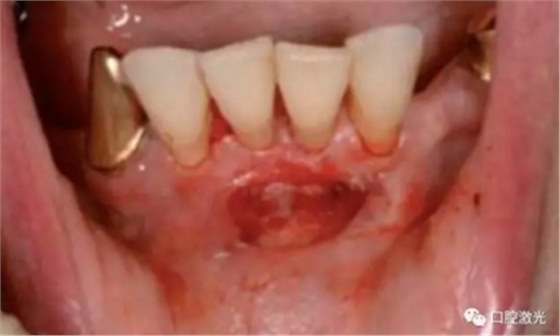

#33,#43显示存在种植体周围炎

激光对#43病变组织气化切除前(左图)后(右图)